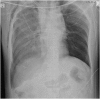

Blunt traumatic transection of the innominate artery is rare. We describe a case of a 36-year-old male who presented to our Emergency & Trauma Center after being struck by a motor vehicle at high speed. Computerised Tomography (CT) scanning after the patient was stabilised facilitated the prompt diagnosis of the injury. The patient underwent open repair by midline sternotomy, with debranching of the innominate artery, using hypothermic circulatory arrest as a neuroprotective measure. The patient was successfully extubated on post-operative day 3, without neurological deficit. We provide our experience as an option for treating any patient that presents with such an injury.